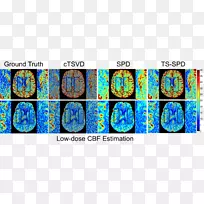

生物医学字体-cbf